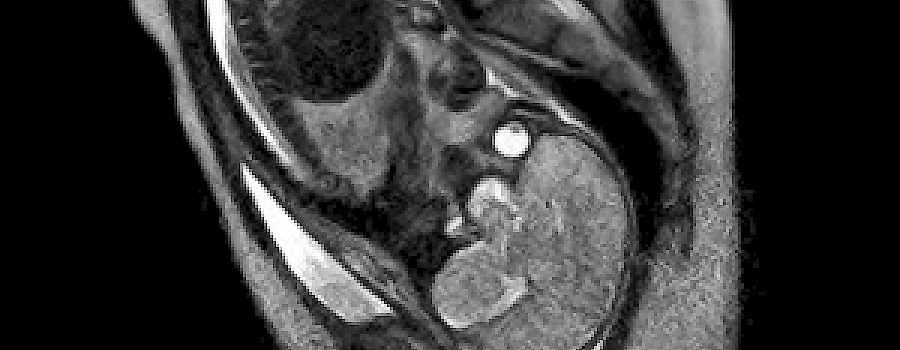

Weltpremiere am Berliner Charité:

Erstmals Geburt im MRT aufgenommen

rockpop 17 Jun, 2011 10:00

Einem Team aus Geburtsmedizinern und Radiologen ist es erstmals gelungen, die Geburt eines Kindes mittels Magnetresonanztomografie (MRT) komplett aufzuzeichnen.